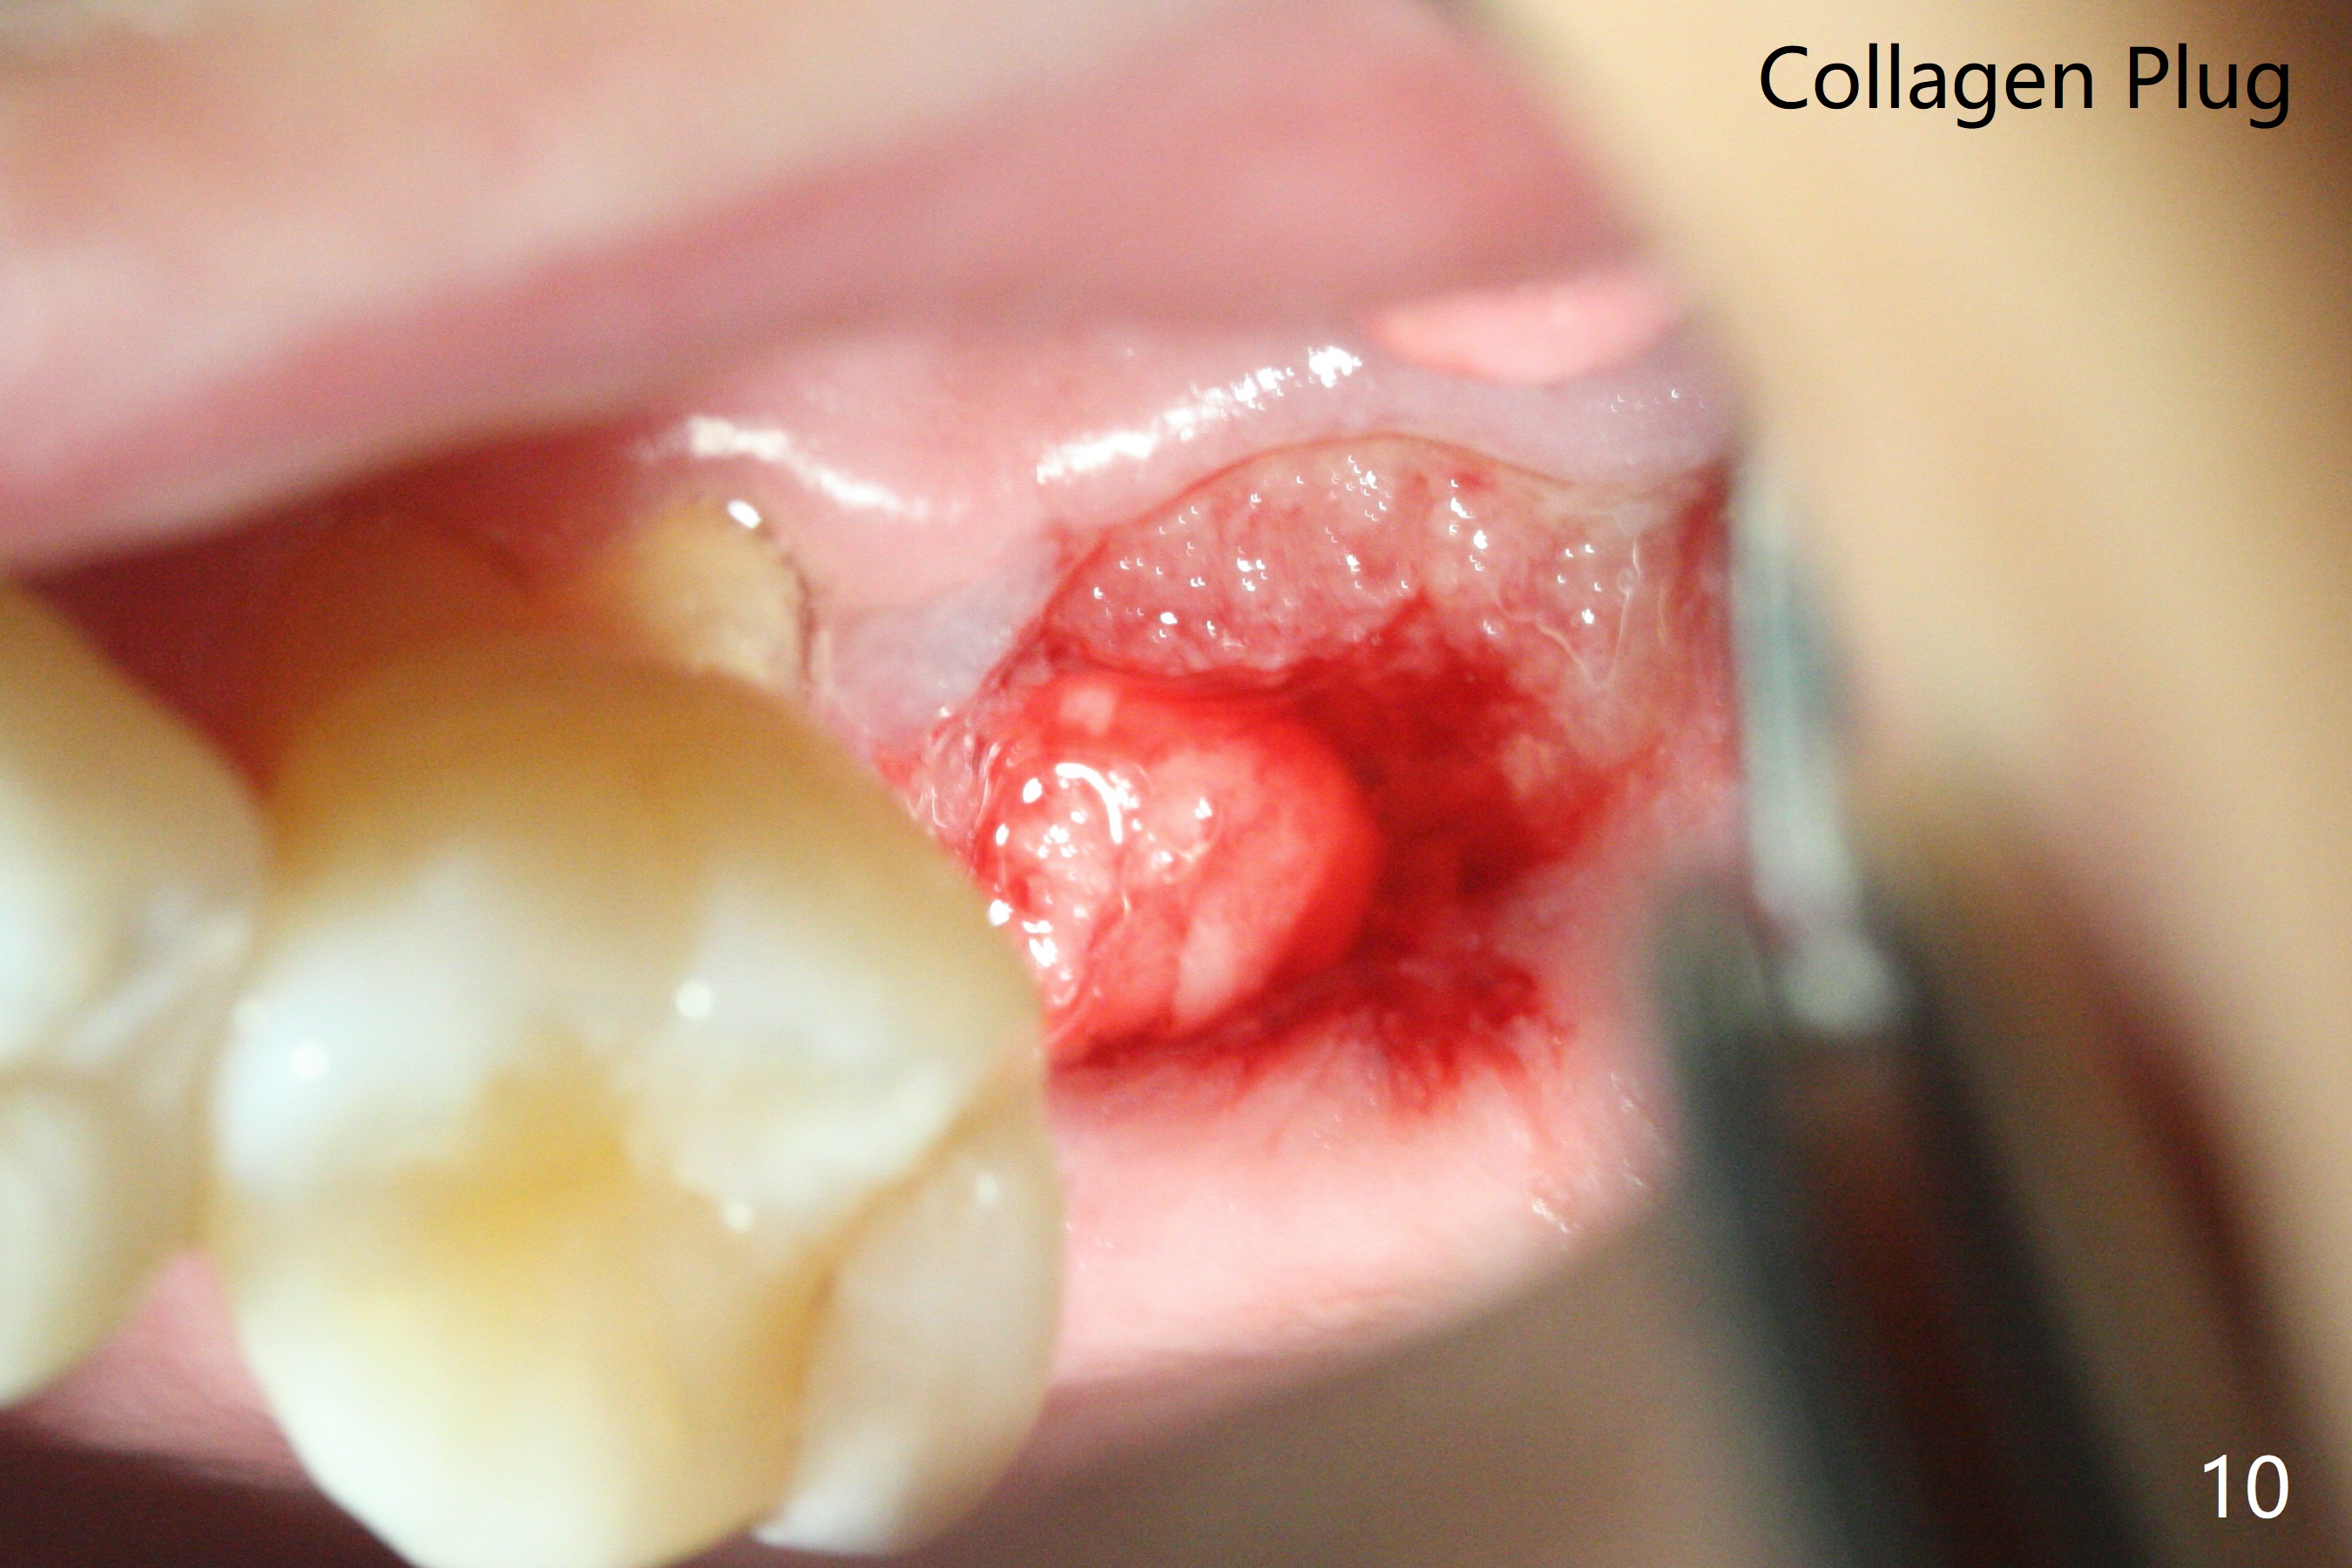

After 4.5x7.3 mm drill with 3 O-rings at #15, use 2.2x7.3 mm one with 2 O-rings. The sinus floor feels like to be perforated, but perio probe does not find the perforation. Nose blowing does not reveal air leakage. It seems fine when 3.0x7.3 mm one with 2 O-rings is being used. The sinus membrane perforates when Magic Sinus Lifter is used. Mixture of autogenous bone (from drills) and allograft does not stick to the periosteal elevator (Fig.1). Forty-minute centrifuge leads to separation of serum (Fig.2 S) from Red Blood Cell layer (R). The separation of the top tube is incomplete with RBC invade the serum layer in a few second (Fig.3 arrow). While the serum layer of the bottom tube is prepared for PRF membrane, a part of the serum layer of the top tube is withdrawn to make sticky bone (Fig.4). The top tube returns to the centrifuge for another 30 minutes to make the second PRF membrane. The first PRF membrane is inserted into the osteotomy and pushed into the sinus with empty feeling, followed by the sticky bone and last by the 2nd PRF membrane. A 5x7.3 mm implant is placed with ~ 10 Ncm, followed by a 6.8x4 mm healing abutment (Fig.5,6 (retrospectively healing screw should be used to reduce sinus-oral communication)). There is no mushroom in the sinus, but hopefully the sticky bone will stick to the bottom of the sinus for maturation. Sinus surgery precaution is provided. Next time tap or dummy implant will be used for sinus lift after initial osteotomy with guide. In fact the patient with diabetes under control has mild cold. The procedure should have been canceled. There is no postop nasal hemorrhage or discharge. The patient returns nearly 8 months postop. The wound is infected. The healing abutment is changed to a healing screw with oral antibiotic. Two weeks later, the area remains infected with symptoms (Fig.7-9). The healing screw is not covered completely. After implant removal, the sinus membrane is perforated. A piece of collagen plug (preferably Osteogen plug) is inserted (Fig.10,11). Because of the concavity, bone graft seems necessary when the wound heals. One week later, perimplantitis develops at #2. The patient is ready for the 3rd placement 1 year 5 months post last implant removal (Fig.12). The bone is 1.8 mm thick, apparently composing of 2 fused cortical plates. Make an incision for both external and internal sinus lift with retraction. Find the old guide to start osteotomy including bone trimmers and use Magic Lifter. If the membrane is broken, open the lateral window to repair with PRF.